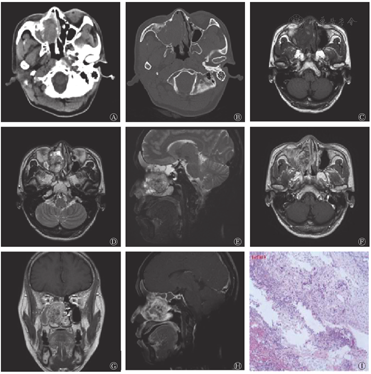

鼻窦CT平扫(图1A、图1B)示右侧鼻腔-筛窦内见团块状软组织密度影,大小为3.0 cm×4.9 cm×4.2 cm,密度不均匀,边界尚清,其内可见小斑片状稍高密度影,边缘见结节状钙化灶,右侧上颌窦、筛窦及鼻腔内骨质破坏、吸收,鼻中隔受推压向左侧偏移,双侧下鼻甲肥大。鼻窦MRI示右侧鼻腔-筛窦内可见团块状信号异常灶,大小为3.0 cm×4.9 cm×4.2 cm,T1加权成像(T1 weighted image,T1WI)横断面图像(图1C)示病灶与邻近肌肉信号相仿,内见小斑片状稍高信号,T2加权成像(T2 weighted image,T2WI)横断面图像(图1D)和T2压脂序列矢状面图像(图1E)示病灶呈混杂高信号,内见斑片状低信号。MRI增强扫描(图1F、图1G、图1H)示病灶呈明显不均匀强化,肿物呈膨胀样生长,邻近右侧眼眶的内侧壁、中鼻甲受压偏移。肿物阻塞右侧额窦、筛窦、蝶窦及上颌窦开口,窦腔内可见斑片状T2WI高信号,右侧眼内直肌未见肿物侵犯征象。左侧上鼻道内见斑片状异常信号,T1WI和T2WI呈低信号,大小为1.1 cm×1.0 cm×1.1 cm,双下鼻甲肥大。

行鼻内镜下右侧鼻腔鼻窦肿物切除术+右侧全组鼻窦开放术,术中见右侧中鼻甲大部分已被吸收,左侧下鼻甲上缘、中鼻道有粉红色新生物。肿物侵犯颅底,颅底骨质尚完整,右侧纸样板已吸收,右侧眼眶筋膜尚完整,右侧上颌窦内侧壁已完全被吸收。手术过程顺利开放右侧全组鼻窦,完整切除病变组织,右侧鼻腔可见灰白色软组织颗粒,行组织病理学检查。组织病理学检查结果诊断为右侧鼻腔肿物,符合脊索瘤的特征(图1I)。免疫组织化学检测结果:胎盘碱性磷酸酶(PLAP,-)、波形蛋白(Vimentin,+)、胶质纤维酸性蛋白(GFAP,-)、P63(-)、酸性钙结合蛋白(S-100,-)、神经特异性烯醇化酶(NSE,-)、肌酸激酶(CK,-)、平滑肌肌动蛋白(SMA,灶性+)、细胞增殖核抗原Ki67(10%+)、CD56(+)、P53(60%+)、CD34(血管+)、上皮膜抗原(EMA,-)、CK8(-)、Desmin(-)、孕激素受体(PR,-)、突角素(Syn,-)、嗜铬粒蛋白A(CgA,-)、白细胞共同抗原(LCA,灶状+)、CD3(小灶状+)、CD5(小灶状+)、CD20(-),糖原(PAS)特殊染色(+)。